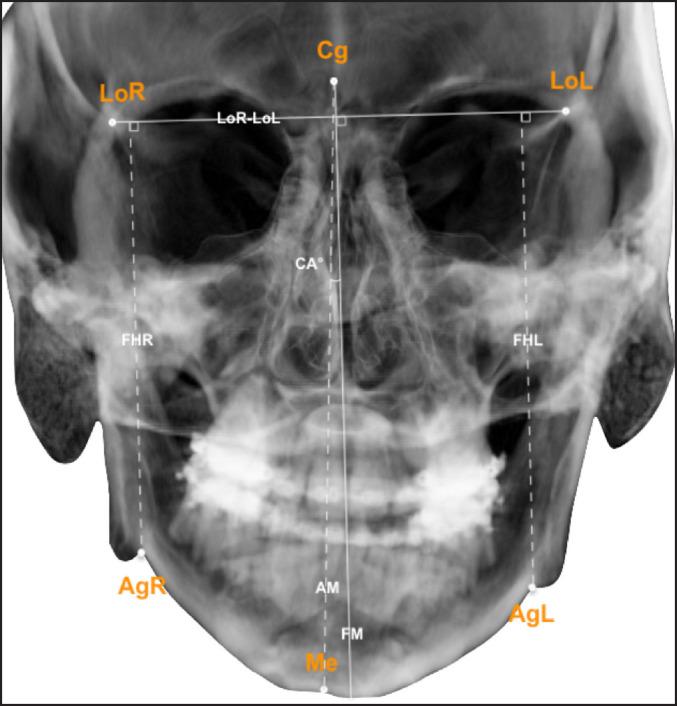

Nineteen patients with juvenile idiopathic arthritis of the temporomandibular joint (TMJ) and dentofacial deformities were included. All patients were treated with combinations of bilateral sagittal split osteotomy, Le Fort I and/or genioplasty, between September 10, 2007 and October 17, 2017. Analysis of patient symptoms and clinical registrations, and frontal/lateral cephalograms was performed pre- and postoperative and long-term (mean: 3.8 and 2.6 years, respectively).

纳入19例患有颞下颌关节(TMJ)青少年特发性关节炎及牙颌面畸形的患者。2007年9月10日至2017年10月17日期间,所有患者均接受了双侧矢状劈开截骨术、Le Fort I型截骨术和/或颏成形术的联合治疗。在术前、术后及长期(平均分别为3.8年和2.6年)对患者症状、临床记录以及正侧位头影测量片进行分析。